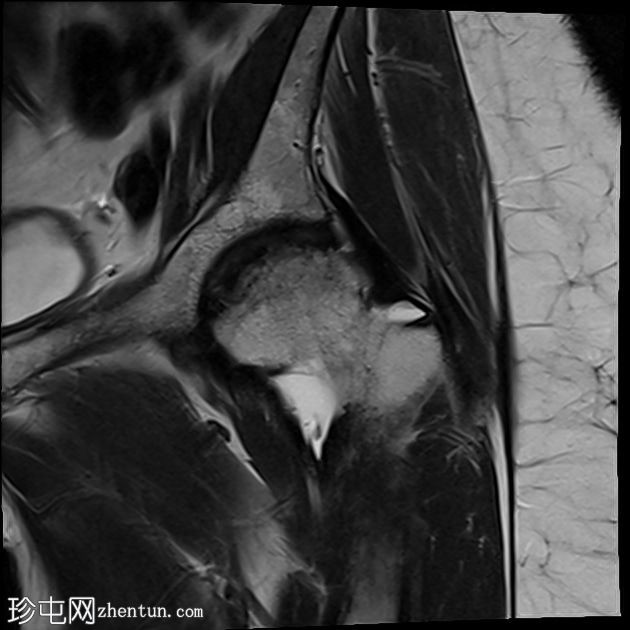

矢状位

(左侧)T2加权像

左侧股骨头:

T1和T2加权像上可见股骨头前上缘呈蛇形低信号,勾勒出一个地理区域,STIR序列上可见邻近骨髓水肿。

软骨下骨折/新月征,关节面局灶性凹陷——符合软骨下塌陷。

关节间隙中央保持完整,但股骨头轮廓异常,系塌陷所致。